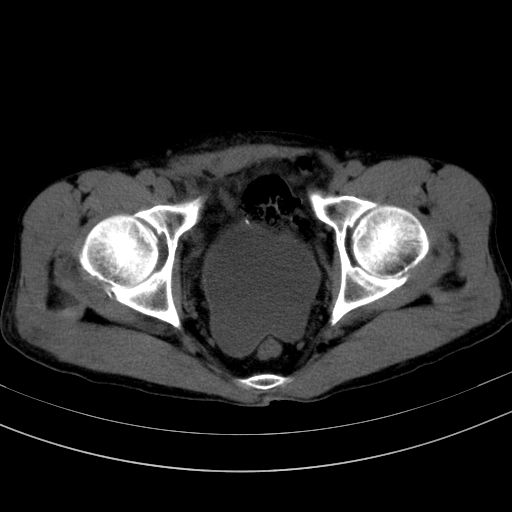

以下是引用37度在2010-1-9 14:37:00的发言:[br]1.双肾囊肿,左肾积水结石,.胆总管轻度扩张;[br]2.病灶在腹膜外,考虑纤维瘤。

以下是引用dyqct在2010-1-9 17:56:00的发言:[br]考虑:1.双肾囊肿,左肾积水结石、旋转不良。[br] 2.右侧腹直肌血肿或纤维瘤。[br]肠道准备不好。做个增强。